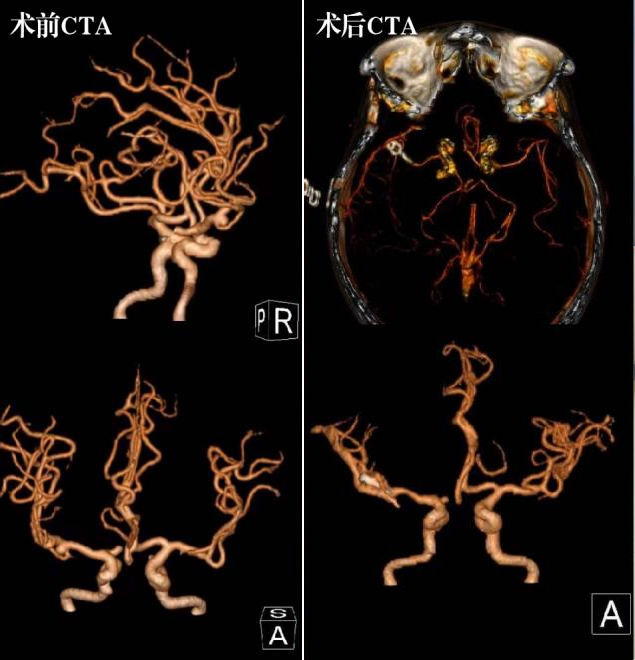

前不久,这位母亲突发意识障碍被送至苏州九院急诊。急诊CTA提示:右侧大脑中动脉的动脉瘤破裂。神经外科副主任邹煜与患者家属沟通后,告知可行血管介入或显微手术夹闭。患者家属考虑后,决定行显微手术夹闭治疗。在手术过程中,邹煜选择右侧额颞翼点入路,通过细致熟练的操作分离动脉瘤瘤颈,752夹闭瘤颈,术后CTA提示动脉瘤夹闭完全,术后病人恢复良好。